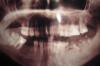

Штаматолог Опубликовано 11 июля, 2007 Поделиться Опубликовано 11 июля, 2007 Названия мне не называли-отправили подумать, т.к. я сразу сказала, что имплантанты очень дорого.Тогда может бюльгельный или гибкий ? Мне еще предлагали вариант с мостом. Вот теперь не знаю что и делать, но семью опустить на 200000 т.руб. я не готова. Спасибо за ответ. Гибкий протез - это не на долго (год-два) - уж туогда лучше бюгель, потому как цена сравнимая. Мост??? Если Вы правильно выложили ОПТГ, то слева снизу там все корни на удаление, какой там мост? Наверху справа отсутствует 7-ка - там вообще кроме имплантации никак больше, если только так и оставить, правда тогда нижняя будет выдвигаться наверх, да и вообще получается будет стоять "в холостую". Подумайте. Все же имплантация дает запас по времени. Вам по-хорошему если: пока удалите все что надо, месяцев 9 на восстановление кости, имплантация, месяца 4-6 на приживление, а потом только протезирование. Получается есть запас года в 1,5. Может за такое время озвученная сумма не будет столь критична для Вашего семейного бюджета. Ссылка на комментарий